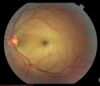

Fundoscopy findings central retinal artery occlusion

- retinal pallor - cherry red spot ## Footnote will have sudden painless vision loss RAPD poor prognosis Order ESR/CRP as can sometimes be due to vasculitis but often are embolic from carotid

fundoscopy central retinal vein occlusion

- extensive retinal haemorrhage "stormy sunset" - dilated turtuous veins - cotton wool spots ## Footnote sudden to gradual, often painless vision loss

47